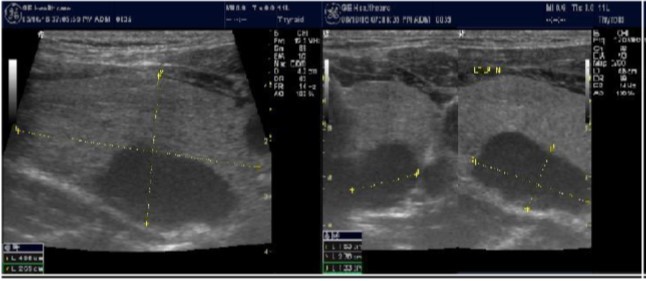

The reported prevalence of nodular thyroid disease depends on the population studied and the methods used to detect nodules 16. Our study population is unique as it is composed entirely of ESKD patients. We also used ultrasound as a method of detecting thyroid abnormalities. In our study the prevalence of thyroid nodular pathology as detected by ultrasound was found to be 57.6% mirror image what reported in the literature as it has been reported that nodules found on ultrasonography suggest a prevalence of 19 to 67%17, 18; and in other publications it has been reported to range from 50% to 70% 7, 8. Figure 3A below shows an Ultrasound detected thyroid nodule.

The prevalence of thyroid nodule is also influenced by age. In one study, 30 % of subjects 19 to 50 years of age had an incidental nodule on ultrasonography19. However, from our work we found that the presence of nodules increases with age. This may explain the reported low incidence of thyroid nodule in the age group 19-50 years. Also, with the widespread use of sensitive imaging in clinical practice, incidental thyroid nodules are being discovered with increasing frequency.

High-resolution ultrasonography (USG) is the most accurate and cost-effective method for evaluating and observing thyroid nodules 3. Although there is some overlap between ultrasound appearance of benign and malignant nodules, certain USG features are helpful in differentiating the two. Iso-or hyper-echogenicity of the thyroid nodule in conjunction with a spongiform appearance is the most reliable criterion for benignity of the nodule on gray-scale ultrasound, Figure 4A. Other features like nodule size <1 cm, width > length, presence of hypoechoic or hyperoechoic halo around the nodule, Figure 4A and Figure 4B, caused by fibrous capsule compressing thyroid tissue, and coarse/curvilinear calcification are less specific but may be useful ancillary signs4 ,6. "Ring down" or "comet-tail" artifact or sign is typical of benign cystic colloid nodule, Figure 520. Perinodular flow or spoke-and-wheel-like appearance of vessels on color Doppler examination is characteristic of a benign thyroid nodule. However, this flow pattern may also be seen in thyroid malignancy. A complete avascular nodule is very unlikely to be malignant 4.